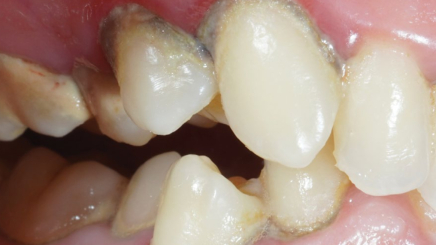

Пародонтит тяжелой степени

Результат через 2 недели

Параметры изменяются в зависимости от процедуры

Хронический пародонтит средней степени тяжести

Вектор терапия по схеме, затем ФДТ 2-3 раза в неделю Сочетание периоскан, вектор-терапии и ФДТ 2-3 раза через неделю.

Гингивит и легкая степень пародонтита

Результат спустя неделю